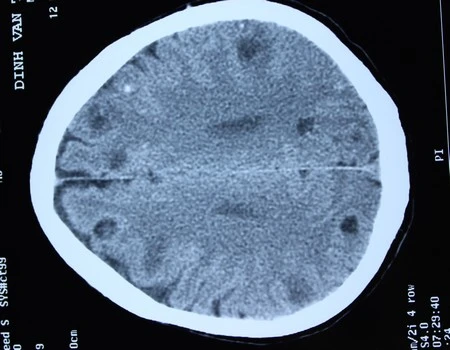

Bệnh nhân nhập viện ngày 12/5 trong tình trạng tri giác lơ mơ, có các cơn co giật. Ông kể thường xuyên ăn lòng lợn tiết canh và rau sống nên các bác sĩ nghi ngờ bị sán não. Trên hình ảnh chụp CT, mỗi lát cắt chụp phát hiện 4-5 ổ sán não, tổng thể có khoảng 50 ổ sán trong não người bệnh.

| Hình ảnh sán làm tổ trong não bệnh nhân. Ảnh:Bác sĩ cung cấp. |